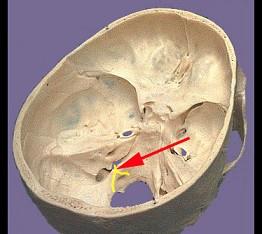

问题 如图箭头所示为哪支脑神经 ( )

选项 A、Ⅹ B、Ⅻ C、Ⅺ D、Ⅷ E、Ⅸ 一、单项选择题

答案 C